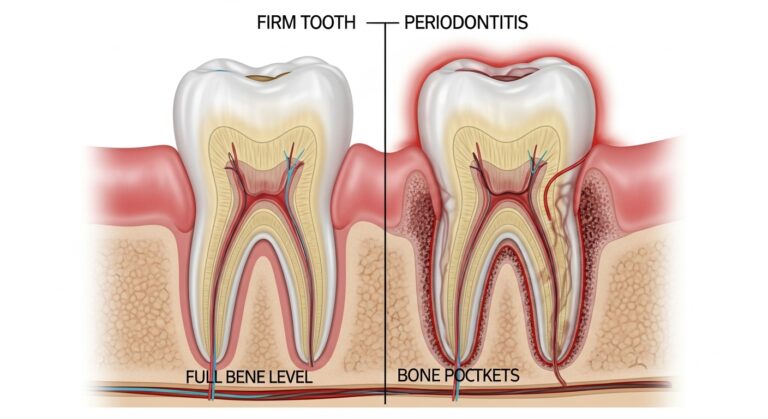

What Is It? Scaling and root planing is the most common and conservative form of treatment for periodontal (gum) disease. Scaling…

What is Periodontics? Periodontics involves the diagnosis, treatment and prevention of gum disease by a general dentist or a periodontist. A…